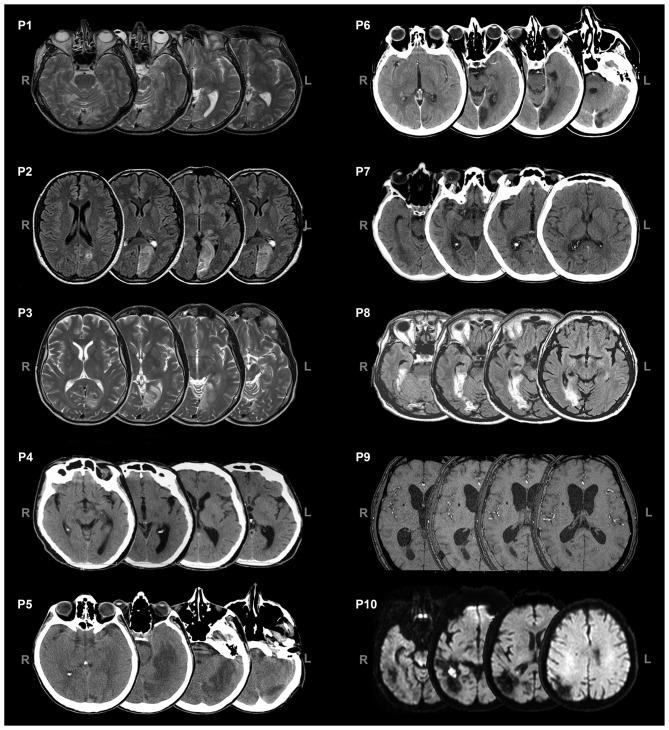

Lateralized post-chiasmatic lesions of the primary visual pathway result in loss of visual perception in the field retinotopically corresponding to the damaged cortical area. However, patients with visual field defects have shown enhanced detection and localization of multisensory audio-visual pairs presented in the blind field. This preserved multisensory integrative ability (i.e., crossmodal blindsight) seems to be subserved by the spared retino-colliculo-dorsal pathway. According to this view, audio-visual integrative mechanisms could be used to increase the functionality of the spared circuit and, as a consequence, might represent an important tool for the rehabilitation of visual field defects. The present study tested this hypothesis, investigating whether exposure to systematic multisensory audio-visual stimulation could induce long-lasting improvements in the visual performance of patients with visual field defects. A group of 10 patients with chronic visual field defects were exposed to audio-visual training for 4 h daily, over a period of 2 weeks. Behavioral, oculomotor and electroencephalography (EEG) measures were recorded during several visual tasks before and after audio-visual training. After audio-visual training, improvements in visual search abilities, visual detection, self-perceived disability in daily life activities and oculomotor parameters were found, suggesting the implementation of more effective visual exploration strategies. At the electrophysiological level, after training, patients showed a significant reduction of the P3 amplitude in response to stimuli presented in the intact field, reflecting a reduction in attentional resources allocated to the intact field, which might co-occur with a shift of spatial attention towards the blind field. More interestingly, both the behavioral improvements and the electrophysiological changes observed after training were found to be stable at a follow-up session (on average, 8 months after training), suggesting long-term effects of multisensory audio-visual training. These long-lasting effects seem to be subserved by the activation of the spared retino-colliculo-dorsal pathway, which promotes orienting responses towards the blind field, able to both compensate for the visual field loss and concurrently attenuate visual attention towards the intact field. These results add to previous findings the knowledge that audio-visual multisensory stimulation promote long-term plastic changes in hemianopics, resulting in stable and long-lasting ameliorations in behavioral and electrophysiological measures.

初级视觉通路视交叉后外侧病变会导致视野中与受损皮质区域视网膜拓扑对应的区域视觉感知丧失。然而,患有视野缺损的患者在检测和定位呈现于盲区的多感官视听刺激对方面表现出增强的能力。这种保留的多感官整合能力(即跨模态盲视)似乎由保留的视网膜 - 丘脑 - 背侧通路所支持。根据这一观点,视听整合机制可用于增强保留回路的功能,因此可能是视野缺损康复的重要工具。本研究对这一假设进行了测试,调查系统的多感官视听刺激暴露是否能诱导视野缺损患者的视觉表现产生持久改善。一组10名患有慢性视野缺损的患者每天接受4小时的视听训练,为期2周。在视听训练前后的几个视觉任务中记录行为、眼动和脑电图(EEG)测量结果。视听训练后,发现视觉搜索能力、视觉检测、日常生活活动中的自我感知残疾和眼动参数均有改善,表明实施了更有效的视觉探索策略。在电生理水平上,训练后,患者对呈现于完整视野的刺激的P3波幅显著降低,这反映了分配到完整视野的注意力资源减少,这可能与空间注意力向盲区转移同时发生。更有趣的是,训练后观察到的行为改善和电生理变化在随访期(平均在训练后8个月)均保持稳定,表明多感官视听训练具有长期效果。这些长期效果似乎由保留的视网膜 - 丘脑 - 背侧通路的激活所支持,该通路促进对盲区的定向反应,既能补偿视野丧失,又能同时减弱对完整视野的视觉注意力。这些结果为先前的研究增添了这样的知识,即视听多感官刺激促进偏盲患者的长期可塑性变化,导致行为和电生理测量的稳定且持久改善。